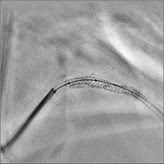

SCORE StentShot* Visualização do stent em alta definição

A excelente visualização do stent com SCORE StentShot aumenta a segurança do paciente e reduz o tempo de tratamento. Este aplicativo fornece uma imagem aprimorada do stent livre de ruído estático, para visualização ideal do stent pós-implantação.